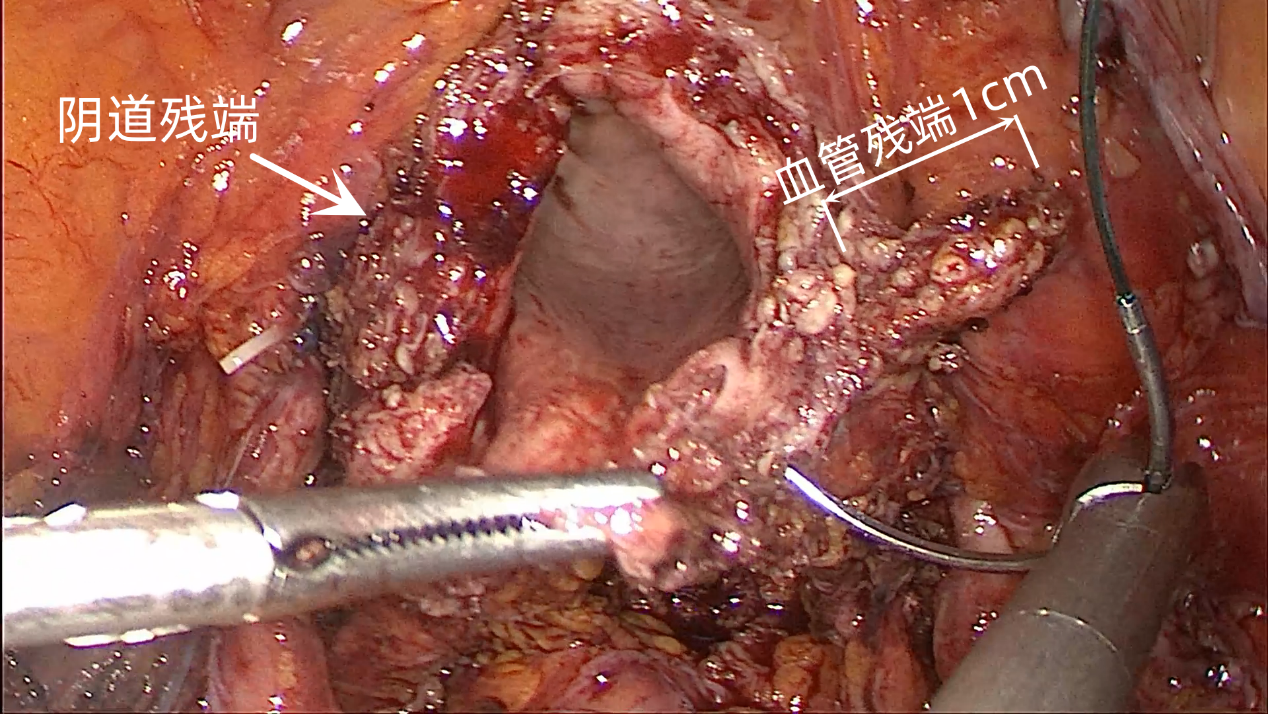

4.4 切断血管时,选择距离杯缘1.5cm左右紧贴宫体切断,向下边推边切至杯缘处,这样可以留有足够的血管断端供后期套扎。在这个过程中,如再次出现出血,继续使用双极电凝止血,但要注意勿超过举宫杯缘,以免对输尿管造成热损伤(图15)

图15